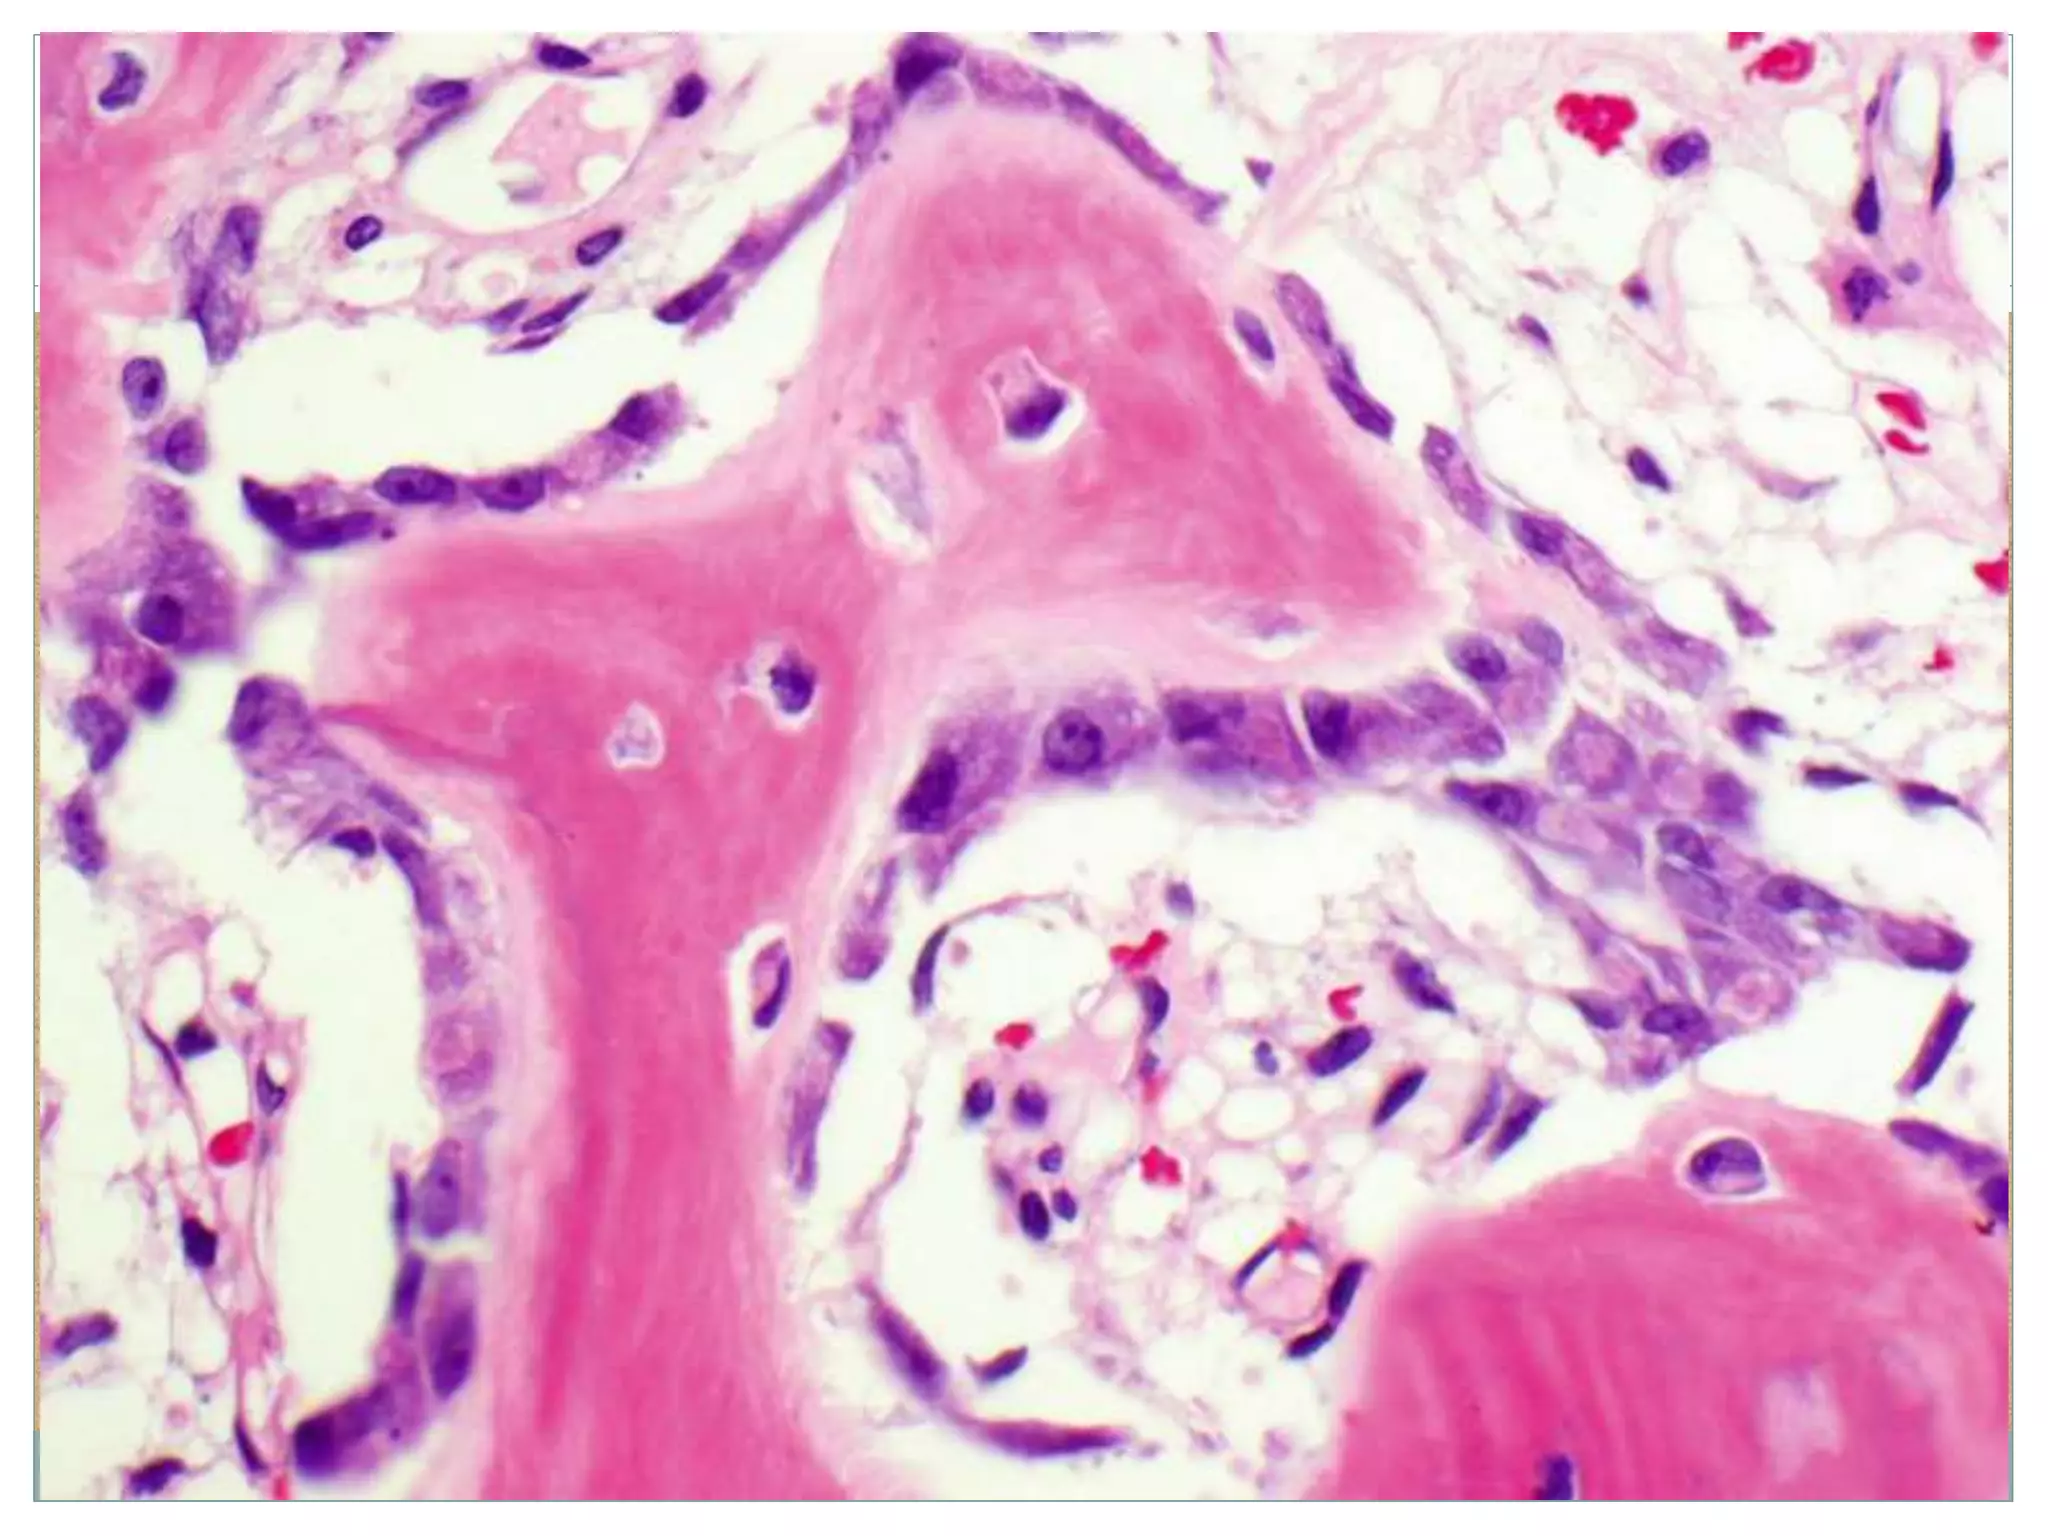

Woven Bone

Under conditions of rapid

turnover, e.g., normal

growth, fracture healing, or

under some pathologic

conditions as illustrated,

osteoid is deposited in

disorganized fashion

and is called woven bone

in contrast to lamellar

bone.

Lamellar bone

Bone Formation Woven Bone Underconditions of rapid turnover, e.g., normal growth, fracture healing, or under some pathologic conditions as illustrated, osteoid is deposited in disorganized fashion and is called woven bone in contrast to lamellar bone. Lamellar bone Woven bone